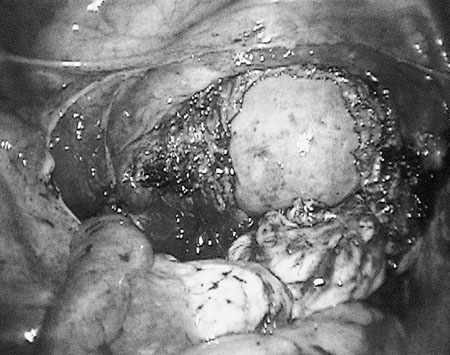

1

Eικόνα 1. Διάνοιξη του περιτοναίου και παρασκευή του ουρητήρα.

2

Eικόνα 2. H μήτρα, η οποία έχει απελευθερωθεί πλήρως, ωθείται μετά τη διάνοιξη

του κολπικού θόλου στον κόλπο.

3

Eικόνα 3. Σύγκλιση του κολπικού

κολοβώματος με ράμμα που περιλαμβάνει και τους ιερομητρικούς συνδέσμους.